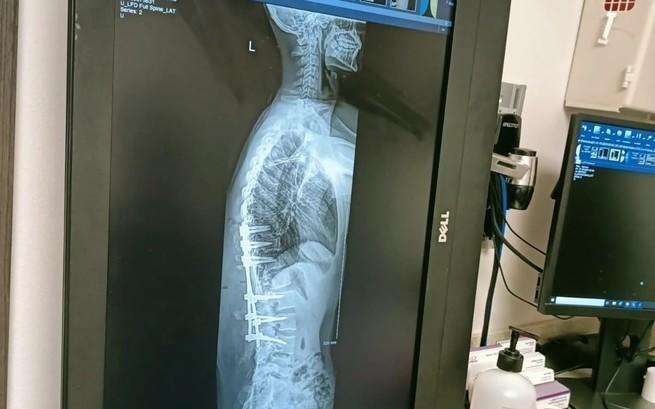

Otrzymaliśmy najnowsze informacje od mamy Szymona. W tej chwili trwają rozmowy na temat Szymona w klinice w USA. Lekarze na konsyliach starają się przewidzieć koszt operacji, które w końcu postawią Szymona na nogi!

W tej chwili wiemy już, że koszt operacji nóg i kręgosłupa to około 1700 000 zł.

Cały czas trwają konsultacje, o których będziemy Was informować na bieżąco. W tej chwili ustawiamy kwotę zbiórki zgodnie z ostatnimi informacjami ze szpitala. Jest to koszt łącznych operacji nóg i kręgosłupa, oraz rehabilitacji pooperacyjnej.

To, co wówczas się wydarzyło, przeszło moje najśmielsze oczekiwania. Dzięki Wam – wielkodusznym ludziom, moim bohaterom, udało się zdobyć ponad 900 000 złotych. Operacja kręgosłupa była konieczna do tego, abym podniósł się z wózka i stanął na własnych nogach, lecz nie doprowadzi mnie ona do pełni zdrowia.

Aby stawiać pewne kroki, wspinać się po górach, pewnie prowadzić samochód i pokonywać wszystkie życiowe przeszkody muszę poddać się również operacji nogi, która ponad dziesięć lat temu zesztywniała, wskutek czego nie mogę jej zginać. Po krótkim czasie od tego wydarzenia zarówno w nodze, jak i pośladku zaczęły zanikać mięśnie. Kiedy pierwsza zbiórka organizowana przez Siepomaga osiągnęła swój cel, od razu wyznaczyliśmy termin operacji kręgosłupa.